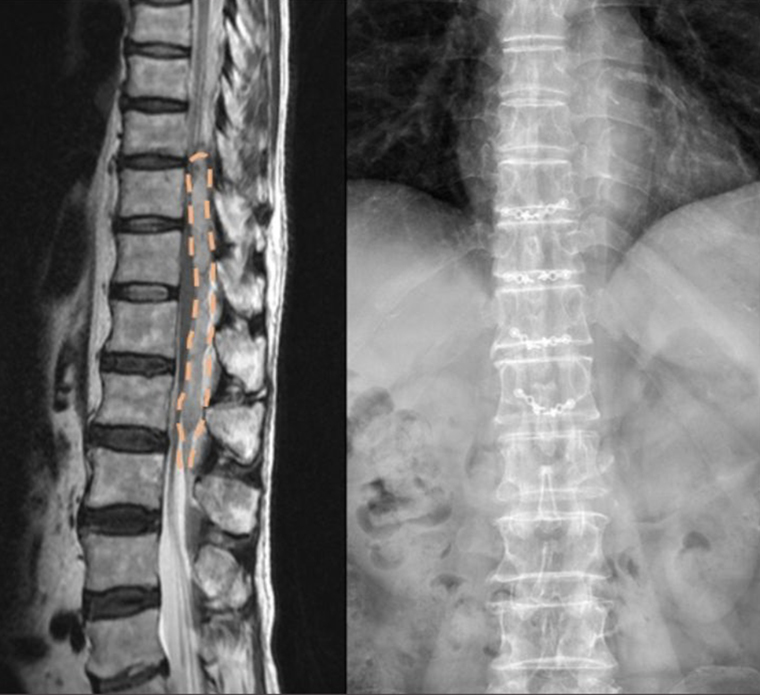

▲左為術前磁振造影顯示硬脊膜外血腫(橘色)造成脊髓壓迫病變,右為術後脊椎X光檢查顯示手術部位骨頭固定良好。(圖/輔大醫院提供)

因病患出現急性下半身癱瘓的神經症狀變化,立即安排胸腰椎核磁共振影像檢查,發現第8胸椎至第3腰椎處出現自發性脊椎硬脊膜外血腫合併脊髓壓迫,疑似有潛在的血管異常問題。神經外科鄭皓中醫師緊急進行第10胸椎至第1腰椎椎板整形手術併血塊清除手術,術後病理切片報告顯示為血塊,並無發現動靜脈畸形或高血管性腫瘤等容易出血之病兆。

鄭皓中指出,因手術中沒有發現明確的出血原因,故再安排脊椎血管攝影檢查,檢查結果未顯示任何異常的脊椎血管病變。患者手術後當天雙下肢肌肉力量隨即改善,1週後恢復下床行走,經由復健治療,出院時已排尿正常、能獨立行走,且日常生活恢復完全自理。